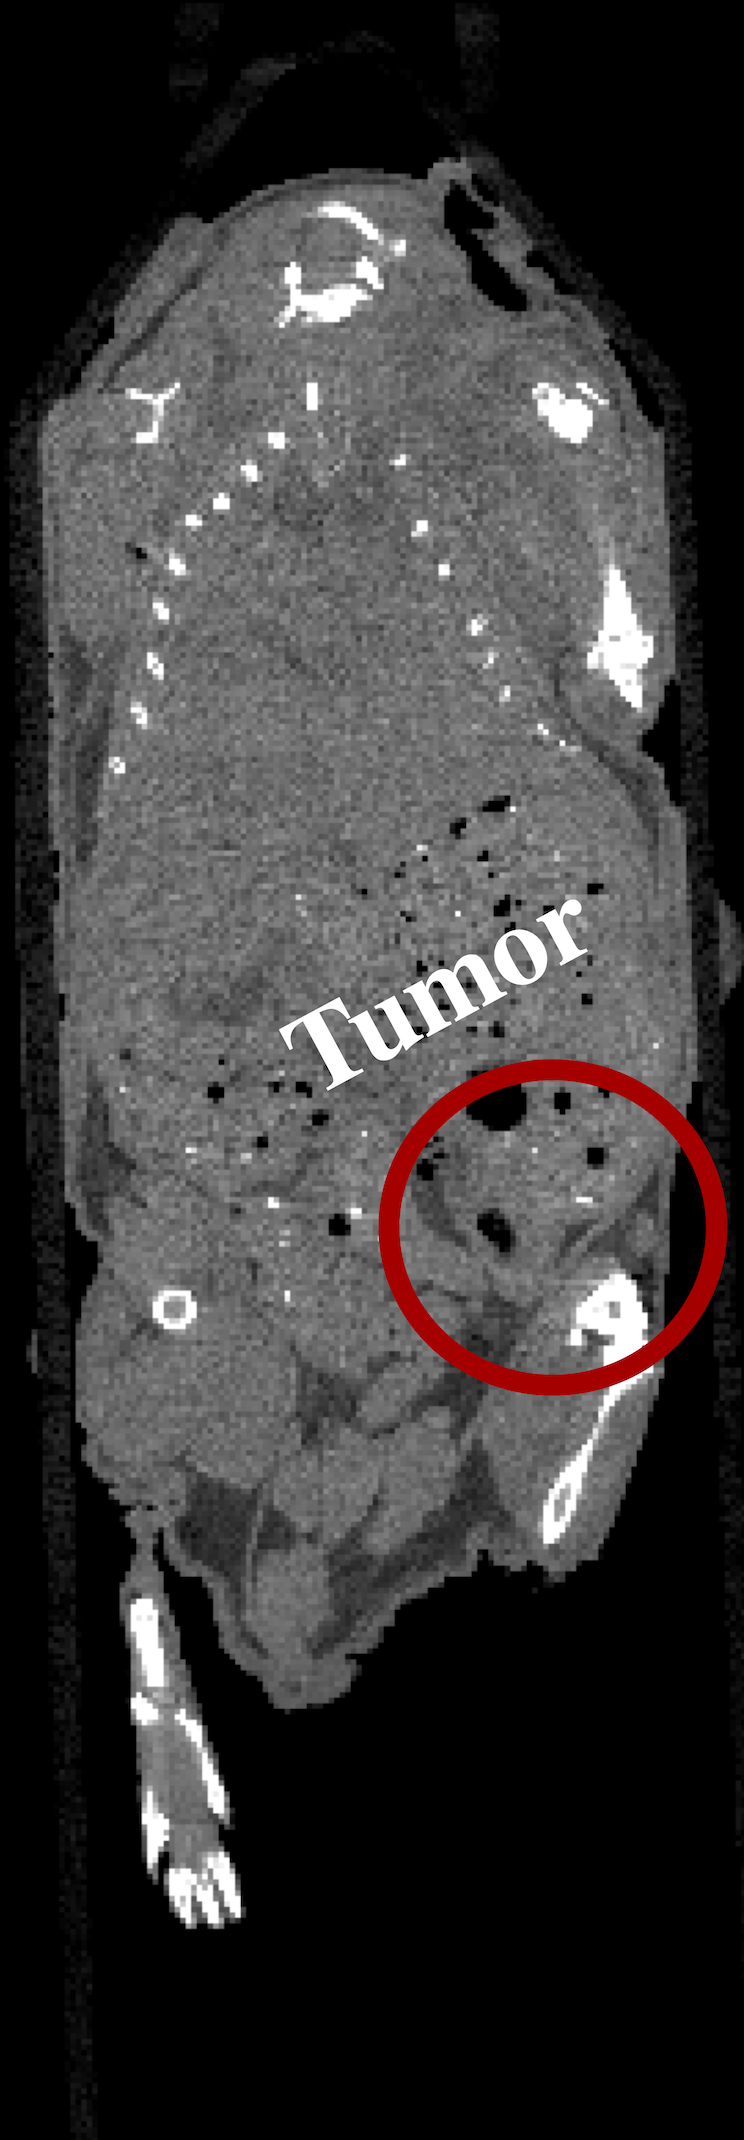

We received two of the mice, hereinafter labeled as A and B, from the UCSF study. Mice A and B were injected with 202020 kBq of 225Ac-Macropa-PEG8(7)-YS5 and 225Ac-DOTA-YS5, respectively. Following injection, mice A and B were euthanized at 222 and 444 days, respectively. The mice were each housed in a 505050 mL falcon tube and stored in a freezer at 7superscript7-7^{\circ}C when not in use.

The two mice were each imaged in the coded aperture and Compton modes to determine the feasibility of using these modalities to assess the daughter redistribution of 225Ac in small animals. The coded aperture and Compton images are overlaid with CT scans. CT imaging was performed separately from the gamma-ray measurements using a MILabs U-CT system; thus, the co-registration is not precise. The following describes the experiments and results in more detail.

In the case of mouse B, the coded aperture and Compton experimental setups were identical to those shown in Fig. 6. The coded aperture measurement of mouse B took place at 444 days post-injection, and data were acquired for 120120120 minutes at each 45superscript4545^{\circ} viewing angle. The total imaging time amounted to 161616 hours, and 3.9×1033.9superscript1033.9\times 10^{3} events were acquired on average at the 218218218-keV emission line of 221Fr at each rotation. The Compton measurement of mouse B took place at 666 days post-injection, and data were acquired for 707070 minutes at each 45superscript4545^{\circ} viewing angle. The total imaging time amounted to 9.39.39.3 hours, and 1.6×1031.6superscript1031.6\times 10^{3} events were acquired on average at the 440440440-keV emission line of 213Bi at each rotation.

Using ML-EM with TV, the two mice were reconstructed in 3-D from the coded aperture and Compton data at the 218218218-keV emission line of 221Fr and 440440440-keV emission line of 213Bi, respectively. Both the coded aperture and Compton images were generated from all eight projections after 250250250 iterations. Figs. 7b-c and 8b-c show the maximum intensity projections (MIP) of the gamma-ray images of mice A and B, respectively. These images are fused with a CT MIP. Furthermore, Figs. 7e-f and 8e-f show coronal slices of the gamma-ray images of mice A and B, respectively. These images are fused with a coronal CT image. The quantification factor, determined from the phantom measurements in Section III-A, was applied to each image so that the intensity scale is in units of percent injected activity per cubic centimeter (%IA/cc). Additionally, the intensity scales are decay corrected to the day of injection.

Figure 8: (a) CT MIP of mouse B fused with the (b) coded aperture (CA) and (c) Compton (CI) MIPs. (d) CT coronal slice of mouse B fused with coronal slices of the (e) CA and (f) CI images. The CA image was generated from a total of 3.1×1043.1superscript1043.1\times 10^{4} events at 218218218 keV, and the CI image was generated from a total of 1.2×1041.2superscript1041.2\times 10^{4} events at 440440440 keV. The intensity scales are decay corrected to the day of injection.